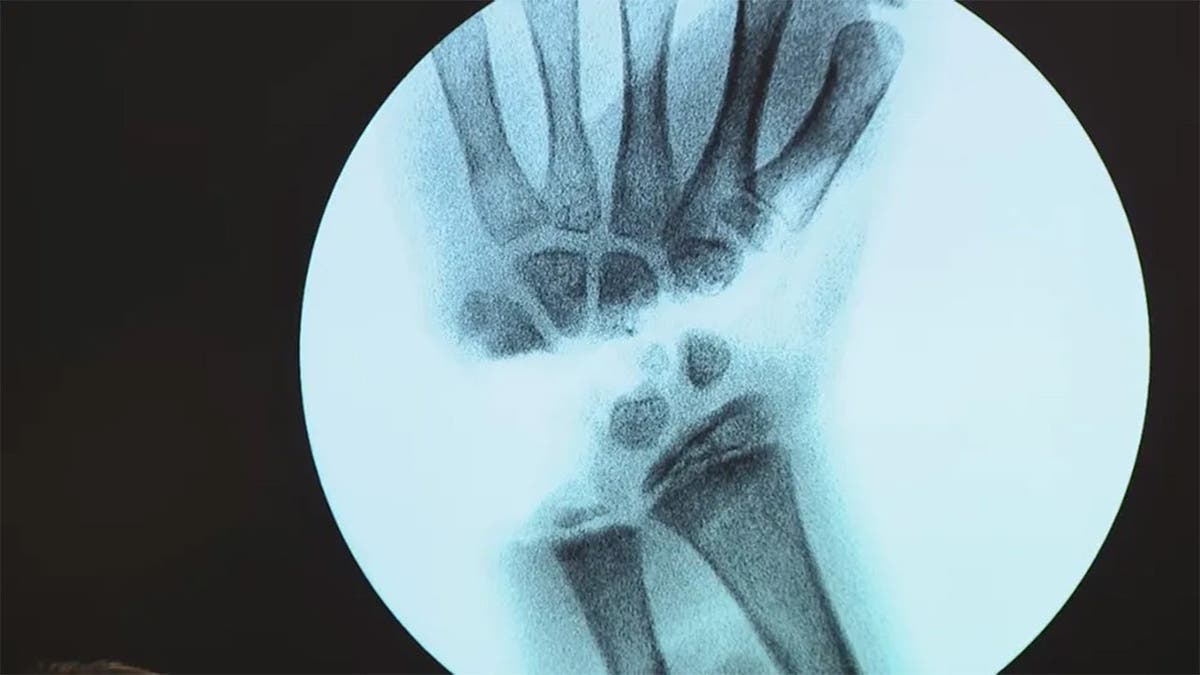

Leah Lendel was 9 when she was bitten during a snorkeling trip with her family. The bite nearly severed her hand off.

Police body camera captured witnesses rushing to help save her life. The girl was airlifted to undergo emergency surgery.

Surgeons were able to successfully reattach her hand following the attack. Leah, now 10, is still working to regain her strength day-by-day.

“I can’t really play piano now, and I can’t pick up more than 8 pounds, but me and my therapist are working for me to get my wrist strength back,” Leah told WZVN.